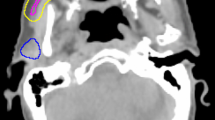

The delivery of therapeutic radiation for HNC has changed significantly over the last two decades. The original technique of conventional 2D radiotherapy (2D-RT) delivered a homogenous dose to both the malignant and normal tissues using paired, opposed radiation beams with limited ability to shape the dose distribution (Fig. 10.2). This led to a very high frequency of early and late normal tissue toxicity [12]. The first RT technique that was investigated to reduce SG toxicity, specifically PG dysfunction, was 3D conformal RT (3D-CRT). This technique uses a multi-leaf collimator (MLC) comprising many narrow, mobile lead leaves, to shape the radiation beam and produce convexities in the dose distribution; however, it is not possible to produce concavities.

Intensity-modulated radiotherapy (IMRT), first described in 1997 [13], is an advanced form of 3D-CRT with the MLC used to define the radiation dose intensity independently for different regions of the target volume. This is achieved by using multiple beam directions, commonly five or seven equi-spaced fields. The shape defined by the MLC is then varied over time. The most frequent methods used are step and shoot, with multiple static fields of different shapes or dynamic MLC with continuous, automated movement of MLCs without treatment interruption. IMRT may also be delivered using arc therapy delivering IMRT with one (360°) or two (720°) continuous rotations of the radiation source around the patient. Examples such as VMAT (Elekta), RapidArc or tomotherapy have the main benefit of a reduction in treatment time [14].

IMRT will therefore define concave and convex shapes (Fig. 10.3) thus allowing high-dose treatment of tumour sites but avoidance of adjacent nontarget normal tissues. The use of IMRT means that delineation of the target and nontarget tissues, patient immobilisation and verification of patient and tumour positions during a course of treatment become even more important. This is to avoid missing the edge of the tumour, which may lead to an increase in recurrence rates (see section “Local disease control with PG-or SMG-sparing IMRT”) with possible overdose of normal tissues.